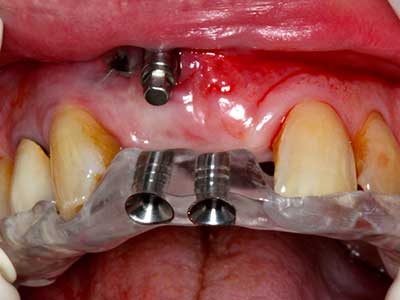

En la extracción de bloques óseos la piezocirugía también presenta ventajas adicionales: Además de la alta precisión en la osteotomía que ya se ha descrito antes, se ha comprobado que el uso de los delgados insertos de sierra resulta especialmente cuidadosas con el hueso. Frente a esto, sobre todo cuando se usan las fresas de Lindemann, cabe esperar pérdidas en la extracción significativamente más altas debido al mayor grosor de la parte frontal del cabezal (Lakshmiganthan, Gokulanathan et al. 2012). La separación basal que se necesita en particular en los injertos de bloque extraídos de forma retromolar se ve facilitada mediante sierras perpendiculares especialmente previstas a tal fin, lo que permite considerar que la cirugía piezoeléctrica es un procedimiento preciso y seguro para la obtención de bloques de hueso en el área retromolar (Happe 2007) (fig. 1-12).

Aplicación: Partición ósea / Cortical Split

El tejido óseo no solo tiene un contenido puramente mineral, sino que también presenta una importante proporción de fibras de colágeno. Esto no solo garantiza una buena resistencia a la presión, sino también una cierta flexibilidad, que puede aprovecharse para la realización de aumentos. En la plastia de expansión clásica a efectos de una partición ósea, la cresta maxilar atrofiada se divide en su eje longitudinal y, tras alcanzar una profundidad de osteotomía suficiente, se extiende con cuidado (fig. 13-16), en un caso ideal sin desperiostizar de forma visible el maxilar (Brugnami, Caiazzo et al. 2014, Stricker, Fleiner et al. 2014). Los sistemas de tornillos y placas con distancia de expansión creciente han demostrado su eficacia para distanciar entre sí las dos tablas óseas por debajo del umbral de rotura. Por regla general, se requieren anchuras de hueso residual de al menos 3 a 4 mm (Chiapasco, Zaniboni et al. 2006) para garantizar una flexibilidad y una cobertura ósea suficientes de los implantes que van a incorporarse. En caso necesario, una osteotomía de descarga vertical unilateral o bilateral puede mejorar la flexibilidad. Como alternativa a la técnica clásica se ha descrito una combinación con otras técnicas de aumento, sobre todo en la parte bucal.

Con el uso de sierras piezoeléctricas la división se efectúa de forma especialmente cuidadosa y sin pérdidas importantes de las dimensiones, por lo que no se han encontrado diferencias significativas entre los implantes realizados en el maxilar dividido y en la cresta alveolar no deficitaria (Chiapasco, Zaniboni et al. 2006, Danza, Guidi et al. 2009). No obstante, precisamente en la partición profunda y limitada de forma local, es preciso asegurarse de que exista una adecuada irrigación por agua para evitar que se produzcan sobrecargas térmicas en las áreas de osteotomía apical.